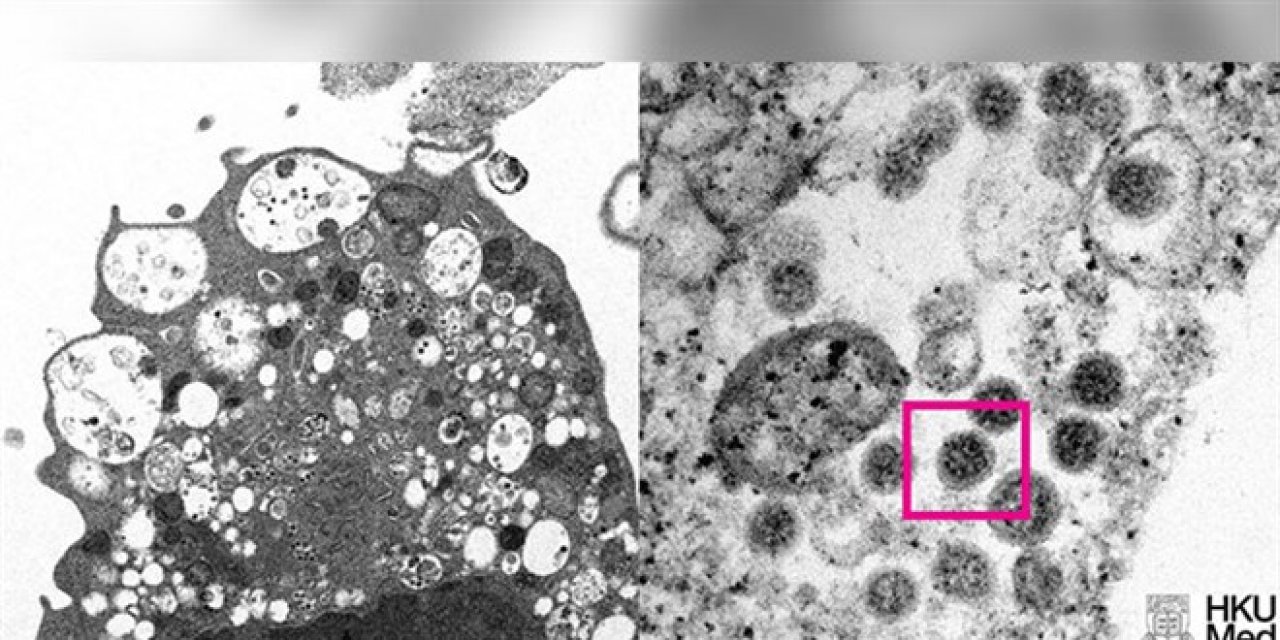

HKUMed’den yapılan açıklamada, araştırmacılar tarafından SARS-CoV-2 virüsünün Omicron varyantının elektron mikroskobu görüntüsünün ortaya çıkarıldığı belirtildi.

Üniversite tarafından yayınlanan fotoğrafın solunda, küçük siyah viral partiküller içeren şişmiş veziküllerle hücre hasarını gösteren, SARS-CoV-2 Omicron varyantı ile enfeksiyondan sonra bir maymun böbrek hücresinin (Vero E6) düşük büyütmeli elektron mikrografının yer aldığı ifade edildi.

Fotoğrafın sağında ise yüzeylerinde korona şekilli sivri uçlara sahip viral partikül kümelerini gösteren enfekte bir Vero E6 hücresinin yüksek büyütmeli elektron mikrografının yer aldığı belirtildi.